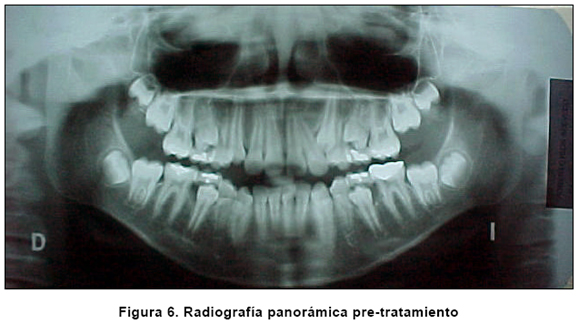

La evaluación de la radiografía panorámica revela una dentición mixta con 32 dientes permanentes y 4 temporales (los gérmenes de los terceros molares están en formación). La proporción corono-radicular es normal y la formación apical es incompleta. La secuencia y la cronología de la erupción son normales. Se aprecia dilaceración radicular (tercio apical) en el incisivo lateral superior derecho.

Después de tres meses de colocar el distalizador, luego de 2 activaciones (se ha conseguido una relación molar clase I) y el desplazamiento espontáneo de los segundos premolares por acción de las fibras transeptales (Figura 5). Se activó más el lado izquierdo, pues de ese lado se requería más espacio para ubicar el canino superior izquierdo. Al comparar las radiografías iniciales con las de control, se puede observar que la distalización de los molares superiores se realizó con muy poca o ninguna inclinación distal de los molares (Figuras 6 y 7).